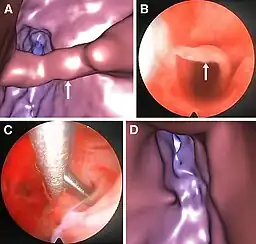

Realizada desde el exterior de la cavidad uterina, la histeroscopia ultrasonográfica virtual es menos traumática e incómoda para las pacientes en comparación con la histeroscopia convencional. Sin embargo, su uso es puramente diagnóstico. Si necesario, una histeroscopia convencional operativa se tiene que programar más tarde. La imagen demuestra un tabique (adherencia) dentro de la cavidad uterina, visualizado por histeroscopia virtual (A) y convencional (B), la intervención por histeroscopia convencional para quitar el tabique (C) y el control posterior por histeroscopia virtual que confirma el éxito de la intervención (D).